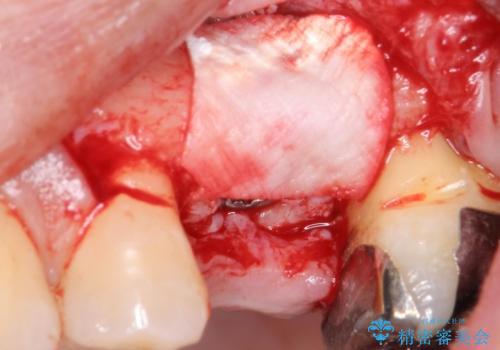

歯茎が腫れる インプラントでの治療

- 左上5/インプラント:242,000円 骨増生:55,000円 カスタムアバットメント:110,000円 インプラント用仮歯:22,000円 ジルコニアクラウン:121,000円 合計550,000円費用は治療当時の料金となります